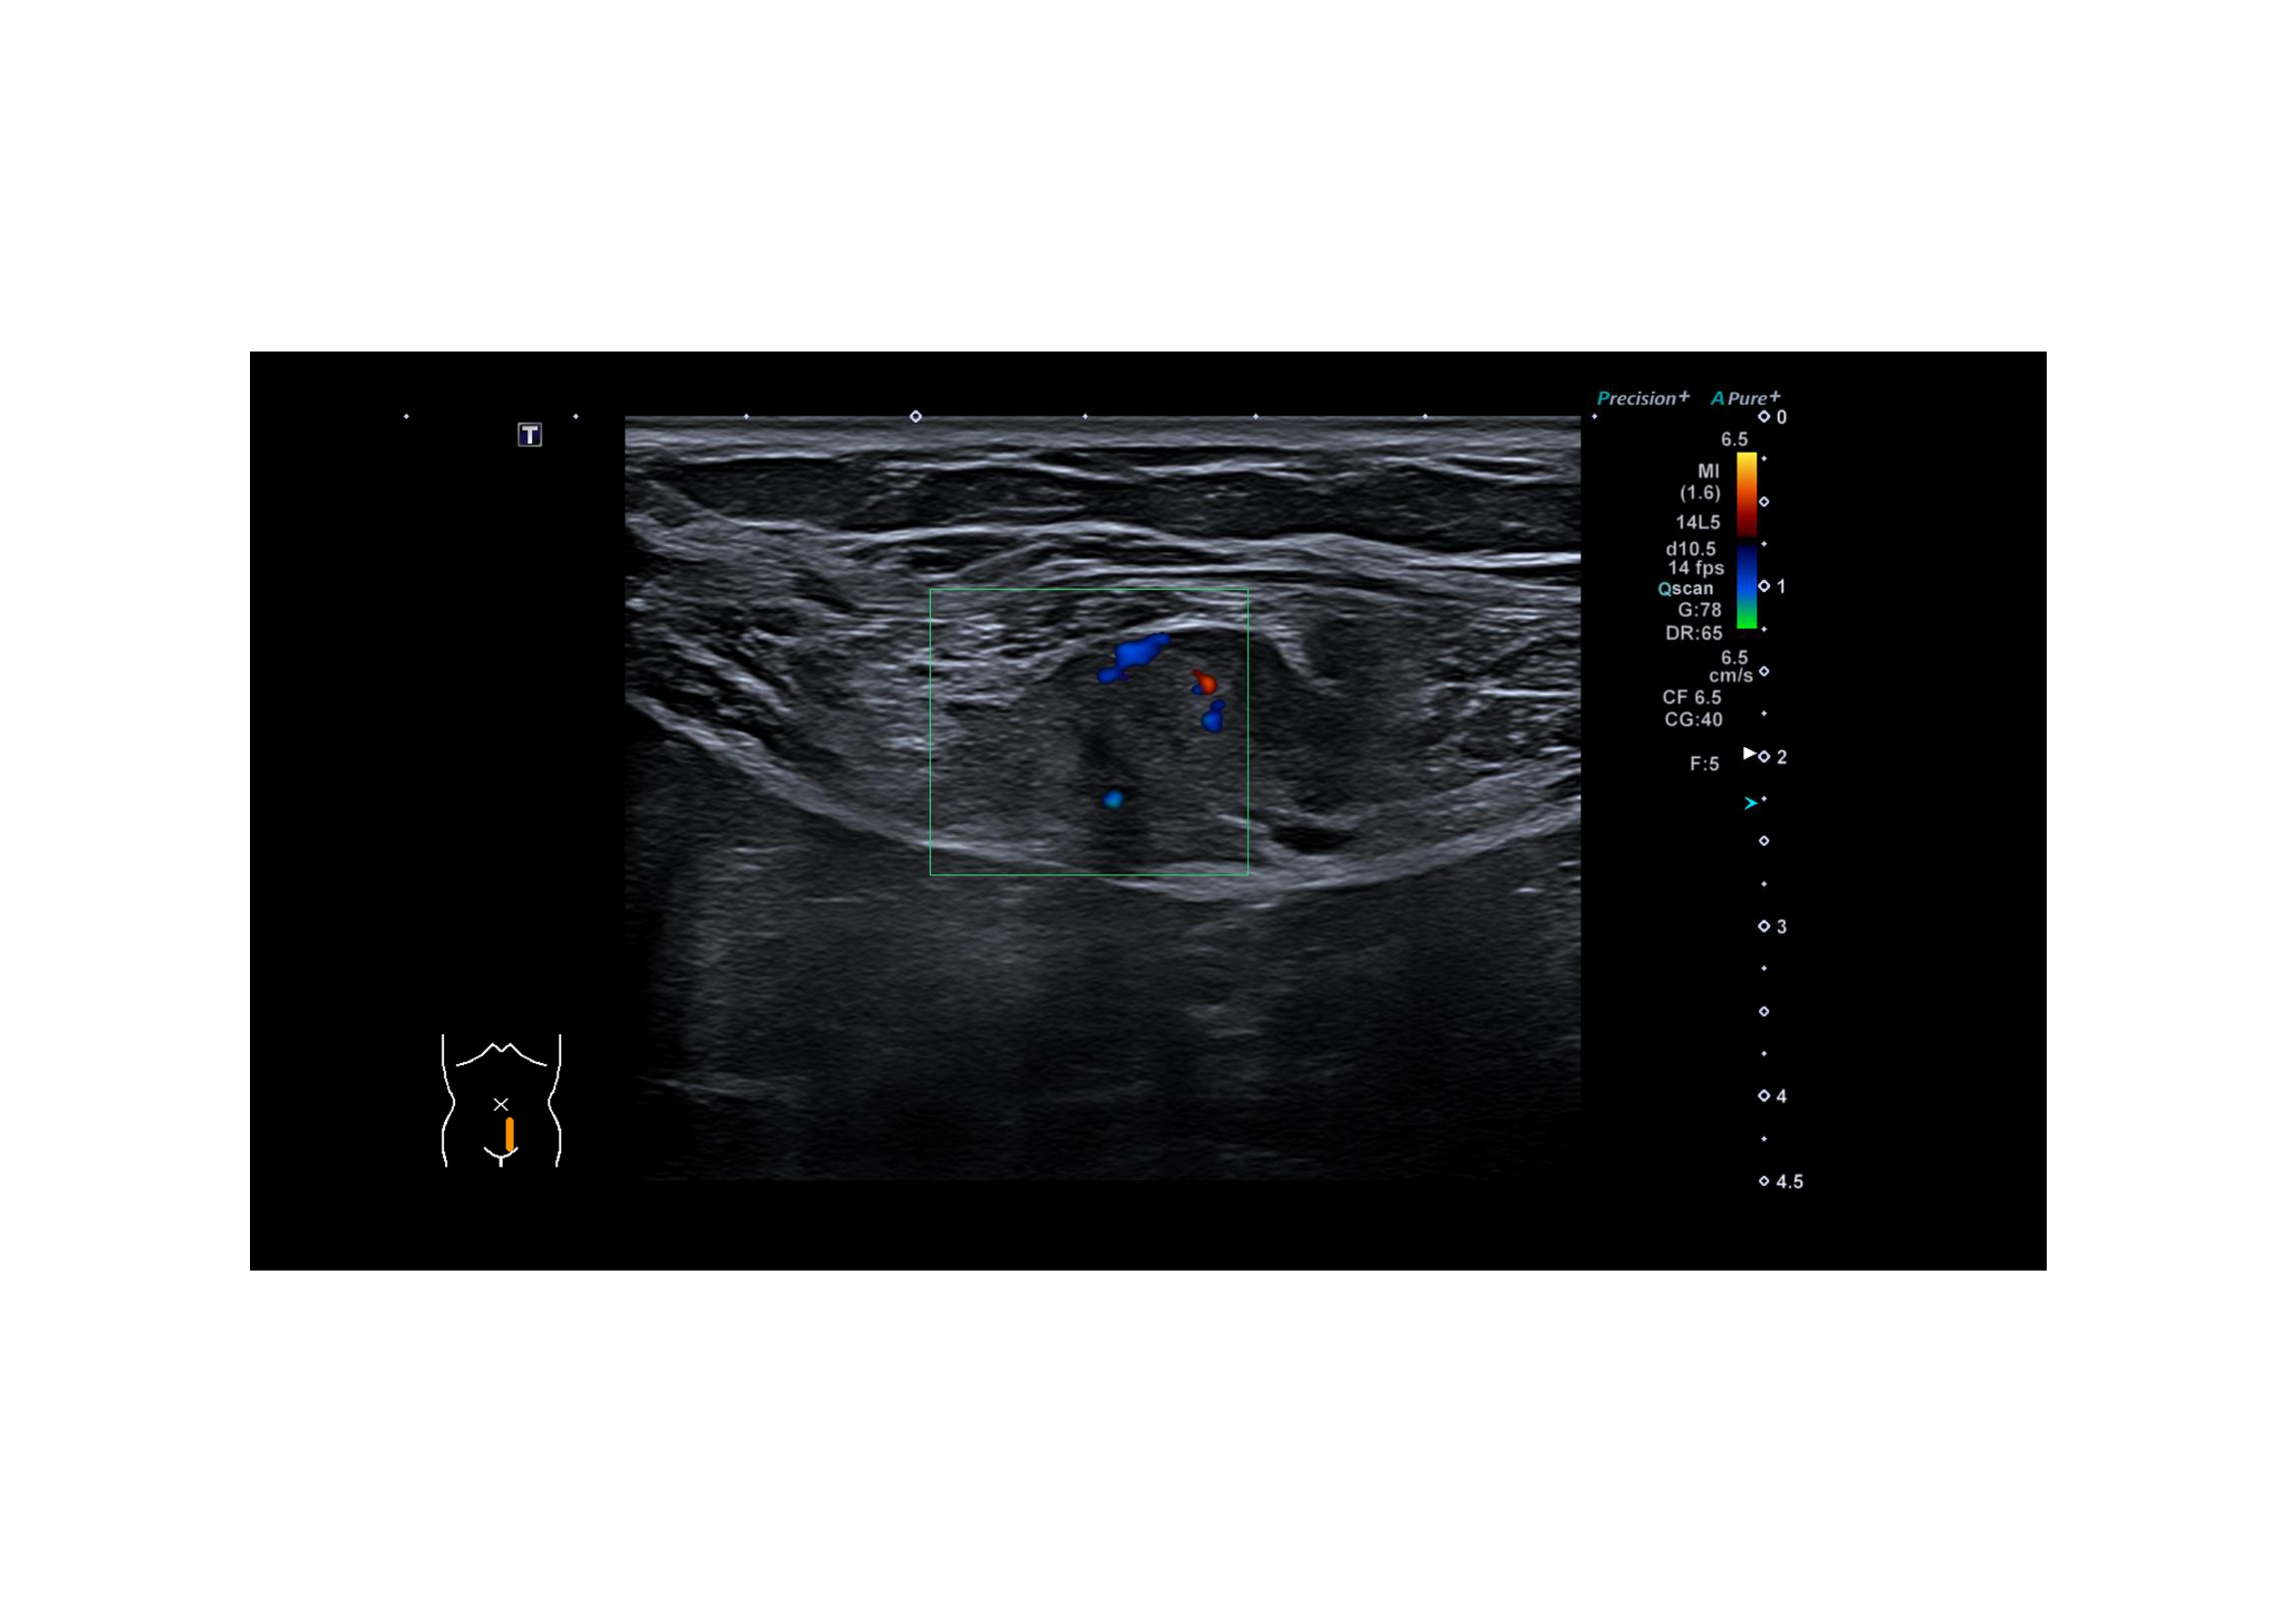

Hallazgos ecográficos

Lesión nodular, de 24 x 13 mm, hipoecogénica con puntos hiperecogénicos internos, márgenes mal definidos, vascularizada, a nivel de musculatura de recto anterior izquierdo sin contactar con cavidad abdominal. Vejiga, no valorable, sin hallazgos de interés.